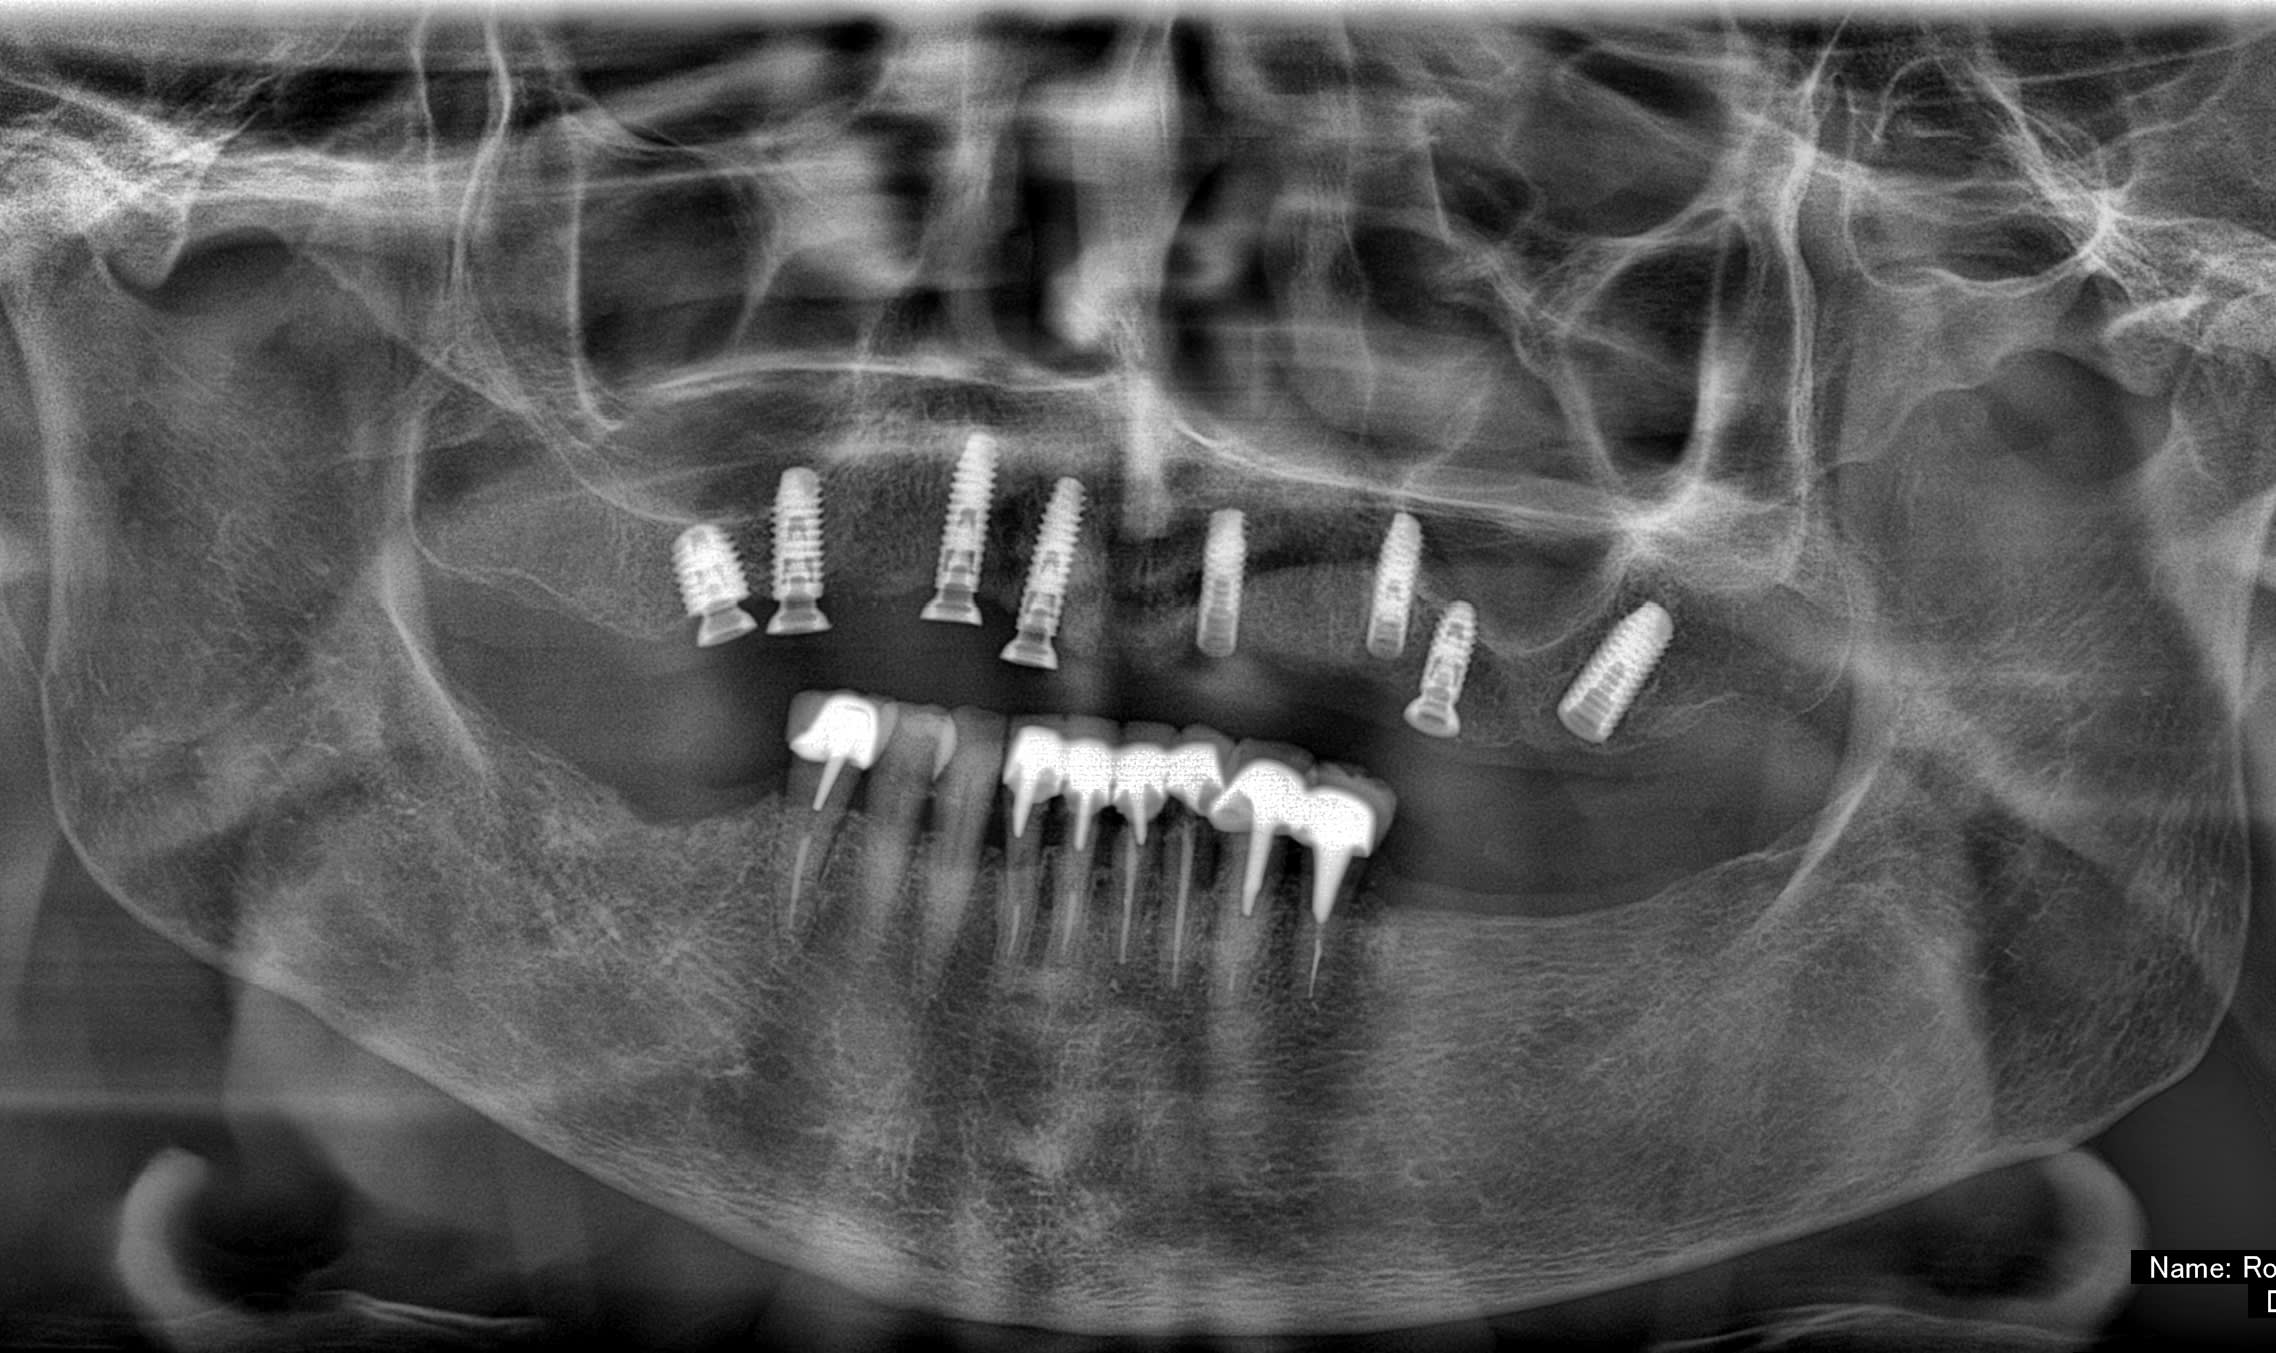

Si tu peux me donner la marque, et le type ça a été posé à Paris (2018?) Dentiste DCD, papiers perdu patiente 85 ans, adressé par un confrère qui pensait à des anthofit, mais ....

Bah, tu fatigues pxav? c'est pas des axiom reg avec ces piliers miltiunits comme ceux des TL????

Ces implants donnent le mal de mer !!! (cf pano !)

au départ je cherchais des Antogyrs , mais mon hésitation, est due au fait que (malgré mon stock de clé) je n'ai rien trouvé pour dévisser le multi unit...Bizarre, vous avez dit bizarre

C'est de l'Anthogyr avec des piliers InLink

Il faut utiliser le tournevis Anthogyr pour accès angulé (tête boule)

Effectivement, c'est le seul truc que je n'utilise pas chez eux...c'est très ingénieux, mais dans le cas présenté, ils ont tous cassés..., j'attends de voir la prothèse d'origine pour savoir d'où vient le soucis.